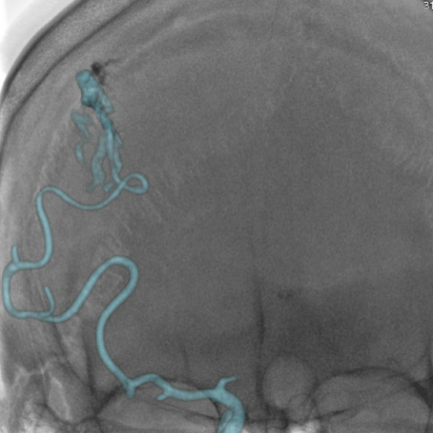

治疗方案及结果: 为了进一步详细观察畸形团形态和大小,需要行3D采集,仅需5秒即可完成血管的三维扫描。  GE提供快速血管提取功能,只需确认血管起点与终点,便可迅速找出供血血管路径,另外,通过使用三维智能路径图可以实时引导治疗过程,

病例点评及临床价值: 由于动静脉畸形团体积较大,且分支血管杂乱无章,因此很难一眼看出畸形团的供血动脉。GE提供快速血管提取功能,只需确认血管起点与终点,便可迅速找出供血血管路径,另外,通过使用三维智能路径图可以实时引导治疗过程,并且在此过程中不论机架、导管床如何变换角度和位置,只要患者相对导管床的位置不变,那么三维智能路径图会始终和患者实际情况完全精准对位,避免了二维路图时需要反复造影的不便。不仅可提高手术精度,还能减少造影剂的使用,节省介入操作时间。